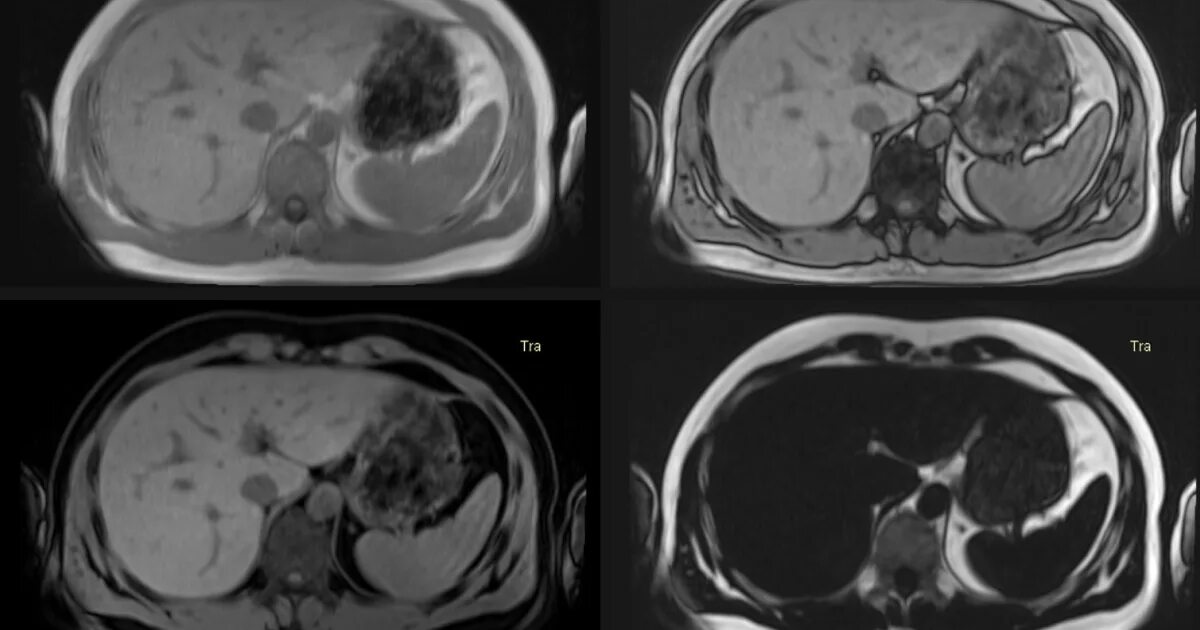

Как выглядит кт с контрастом